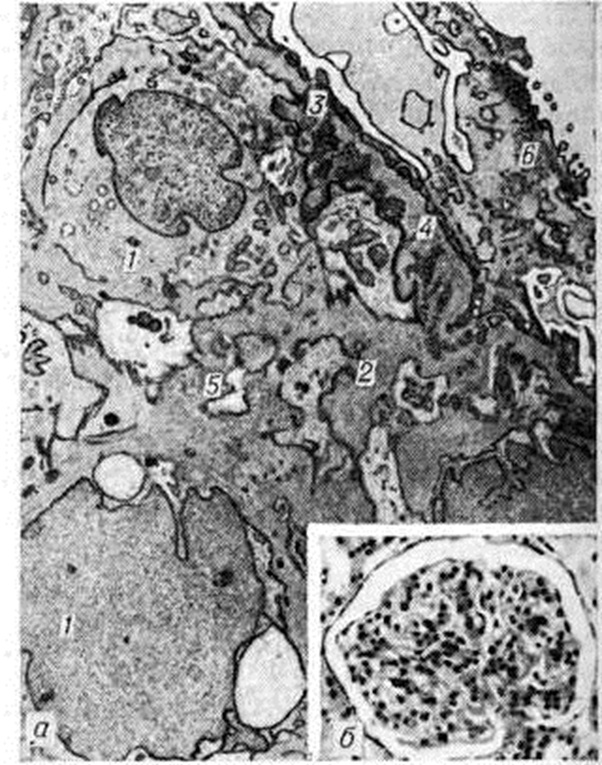

Рис. 3.

Микропрепарат (а) и электронограмма (б) почки при экстракапиллярном продуктивном гломерулонефрите: а — пролиферация нефротелия с образованием характерных «полулуний» (J) в полости клубочковой капсулы (окраска гематоксилин-эозином); ×200; б — в цитоплазме подоцита (1) большое количество фаголизосом (2); ×20 000.

При преобладании пролиферации эпителия капсулы клубочка возникает пролиферативный экстракапиллярный Гломерулонефрит, который рассматривают как морфологически аналог злокачественного «подострого» или прогрессирующего острого Гломерулонефрит [Дженнингс (R. В. Jennings), Эрл (D. P. Earle)]. Этот вид Гломерулонефрит имеет достаточно характерную морфологию в виде так называемый полулуний из пролиферирующих клеток (рисунок 3 а), которые заполняют просвет капсулы и сдавливают капиллярные петли клубочка. Пролиферация клеточных элементов клубочков обычно сочетается с экссудативными экстракапиллярными процессами, появлением среди клеток нитей фибрина. При этом выявляется фагоцитарная функция подоцитов, в цитоплазме которых с помощью электронной микроскопии можно обнаружить множество фаголизосом (рисунок 3 б): перерабатывающих продукты белкового распада. Экстракапиллярная пролиферация возникает как реакция на резкое повреждение капиллярных петель клубочка, которое для экстракапиллярных форм Гломерулонефрит является правилом. Довольно рано клетки «полулуний» претерпевают фибропластическое превращение. В пролиферат врастает соединительная ткань со стороны капсулы, происходит рубцовая облитерация полости капсулы, что ведёт к гибели клубочка.